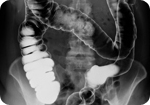

(NewsTarget) Researchers believe that they may have uncovered the function for the appendix, which has long been thought to be superfluous: the organ may act as an incubator for beneficial bacteria that aid the body in digestion.

Writing in the Journal of Theoretical Biology, researchers from Duke University Medical School speculate that the appendix provides a reservoir of beneficial microbes so that the body can replenish its supply in case a disease such as cholera or amoebic dysentery causes the bacteria in the lower gut to be purged.

The researchers observed that the appendix is located just beneath the large intestine, in a spot that food and bacteria usually flow past in only one direction. This would be an ideal location for the hypothesized function.